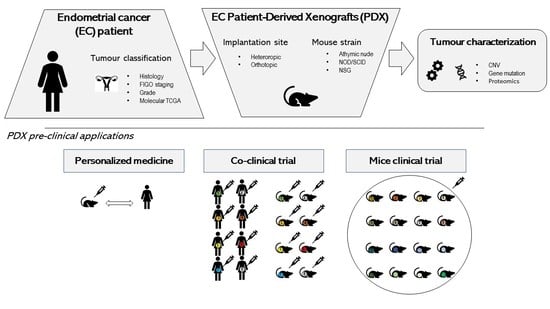

2. Endometrial Cancer PDX Models

2.1. Strategies for EC PDX Model Development

2.4. Use of EC PDX Models in Preclinical Studies